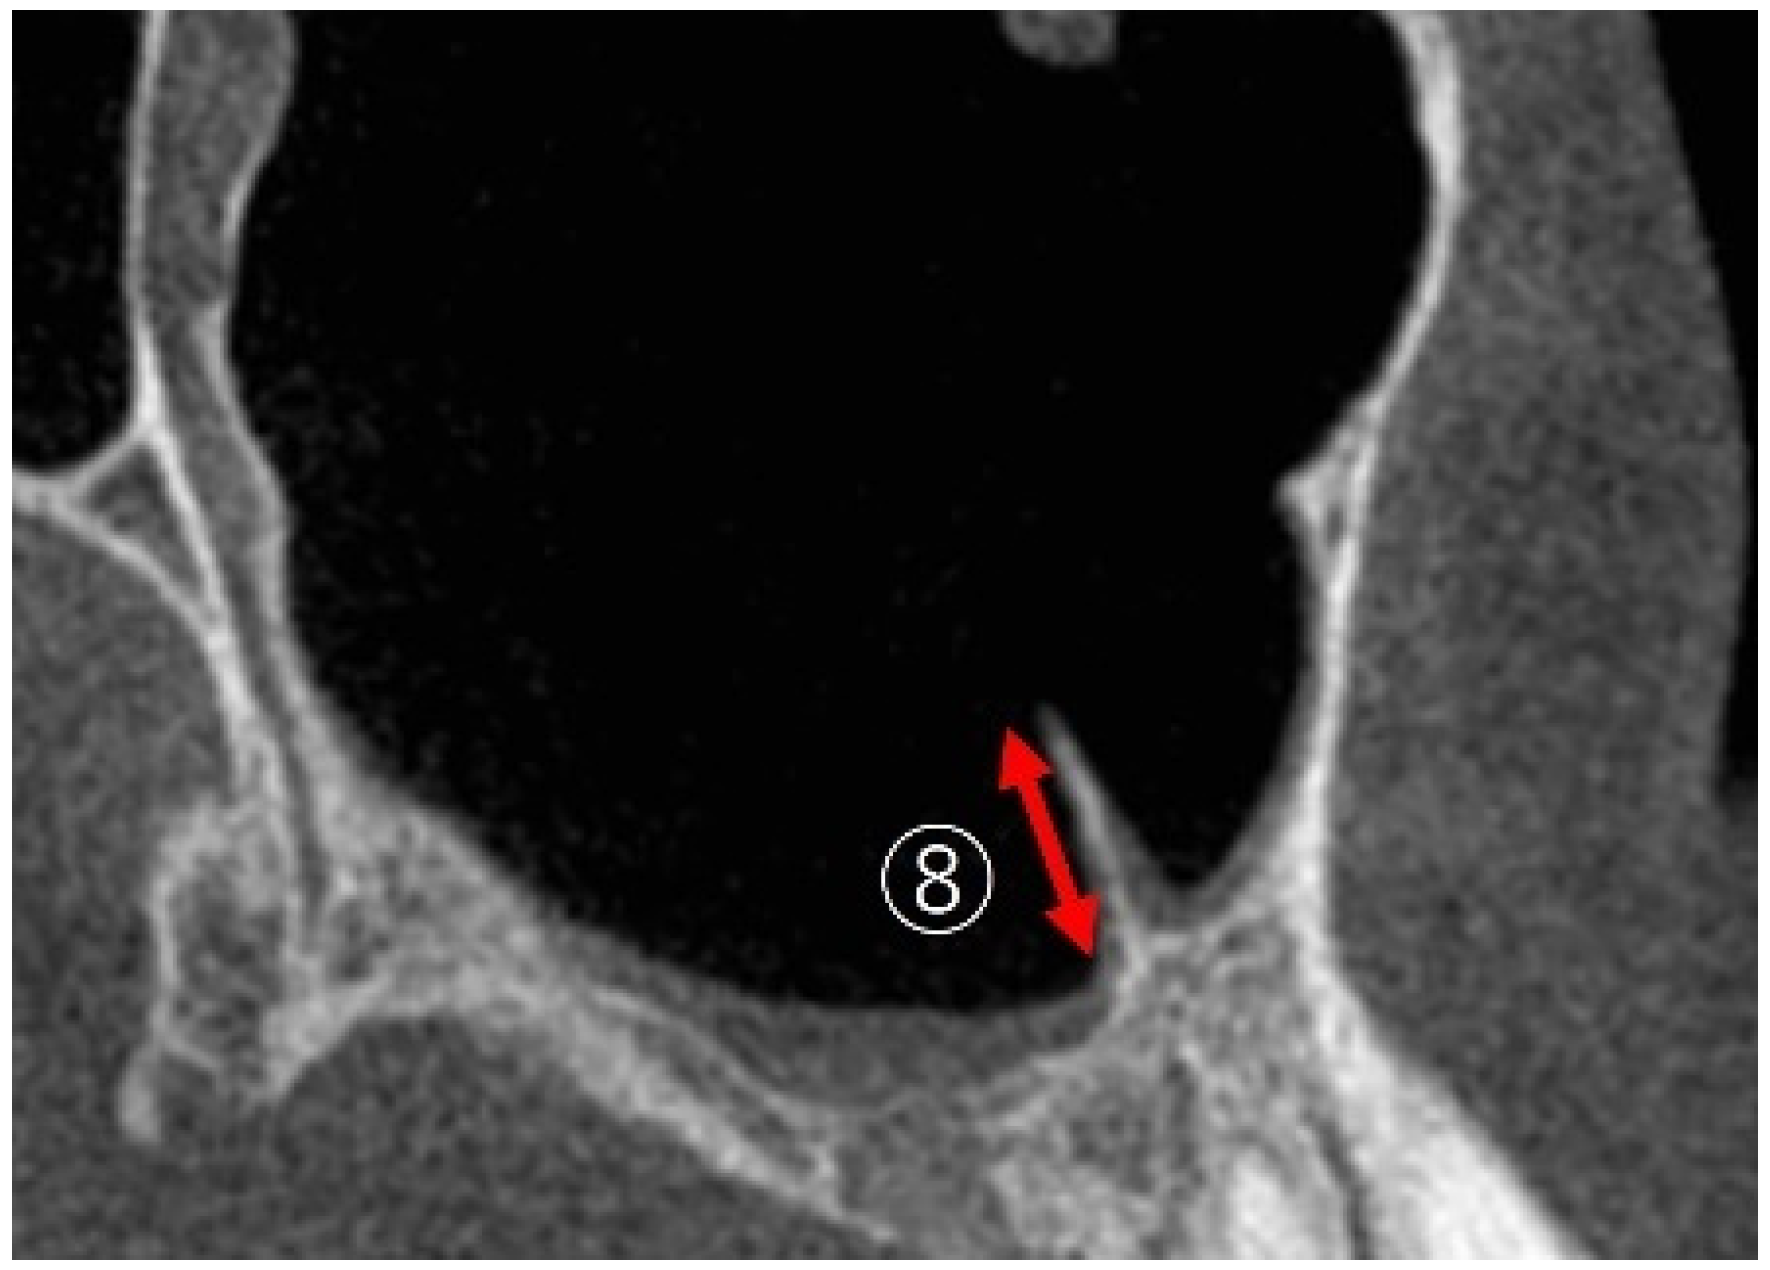

2.3.4. Linear Measurements of Maxillary Sinus Length

2.3.5. Maxillary Sinus Septa